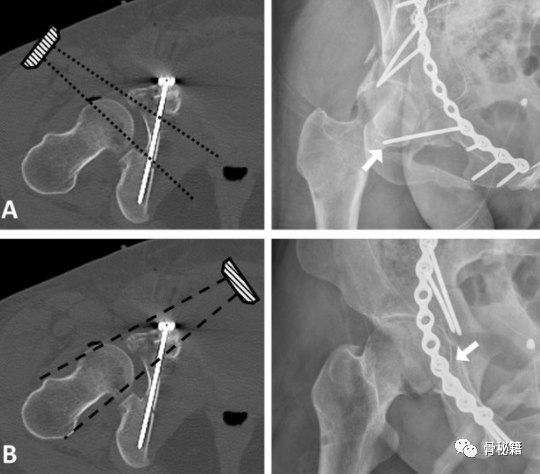

入钉角度

髋臼内缘的螺钉角度每个人都不太一样

文献研究表示15-45°都有

术中透视

通过正位,入口,出口位进行监控

术后检验,当然是CT扫描啦,就看你的自信程度了